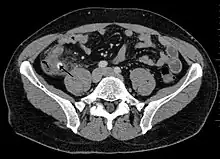

Computed tomography

Where it is readily available, computed tomography (CT) has become frequently used, especially in people whose diagnosis is not obvious on history and physical examination. Although some concerns about interpretation are identified, a 2019 Cochrane review found that sensitivity and specificity of CT for the diagnosis of acute appendicitis in adults was high.[61] Concerns about radiation tend to limit use of CT in pregnant women and children, especially with the increasingly widespread usage of MRI.[62][63]

The accurate diagnosis of appendicitis is multi-tiered, with the size of the appendix having the strongest positive predictive value, while indirect features can either increase or decrease sensitivity and specificity. A size of over 6 mm is both 95% sensitive and specific for appendicitis.[64]

However, because the appendix can be filled with fecal material, causing intraluminal distention, this criterion has shown limited utility in more recent meta-analyses.[65] This is as opposed to ultrasound, in which the wall of the appendix can be more easily distinguished from intraluminal feces. In such scenarios, ancillary features such as increased wall enhancement as compared to adjacent bowel and inflammation of the surrounding fat, or fat stranding, can be supportive of the diagnosis. However, their absence does not preclude it. In severe cases with perforation, an adjacent phlegmon or abscess can be seen. Dense fluid layering in the pelvis can also result, related to either pus or enteric spillage. When patients are thin or younger, the relative absence of fat can make the appendix and surrounding fat stranding difficult to see.[65]